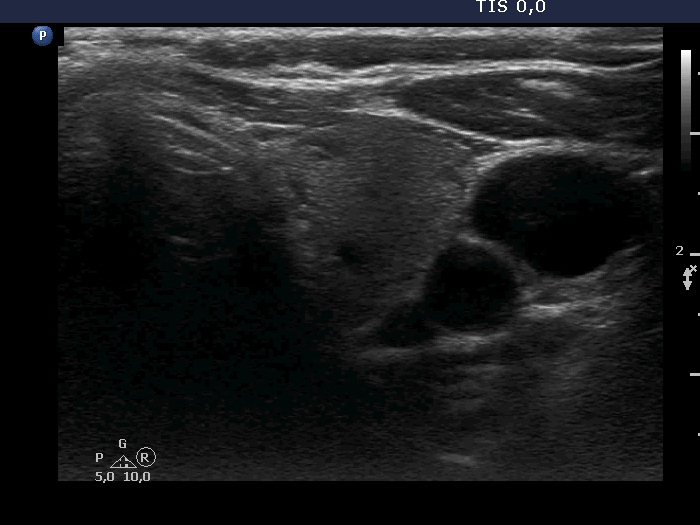

Right lobe, longitudinal scan

Left lobe, transverse scan. This lobe has no lesion of clinical or oncological importance.